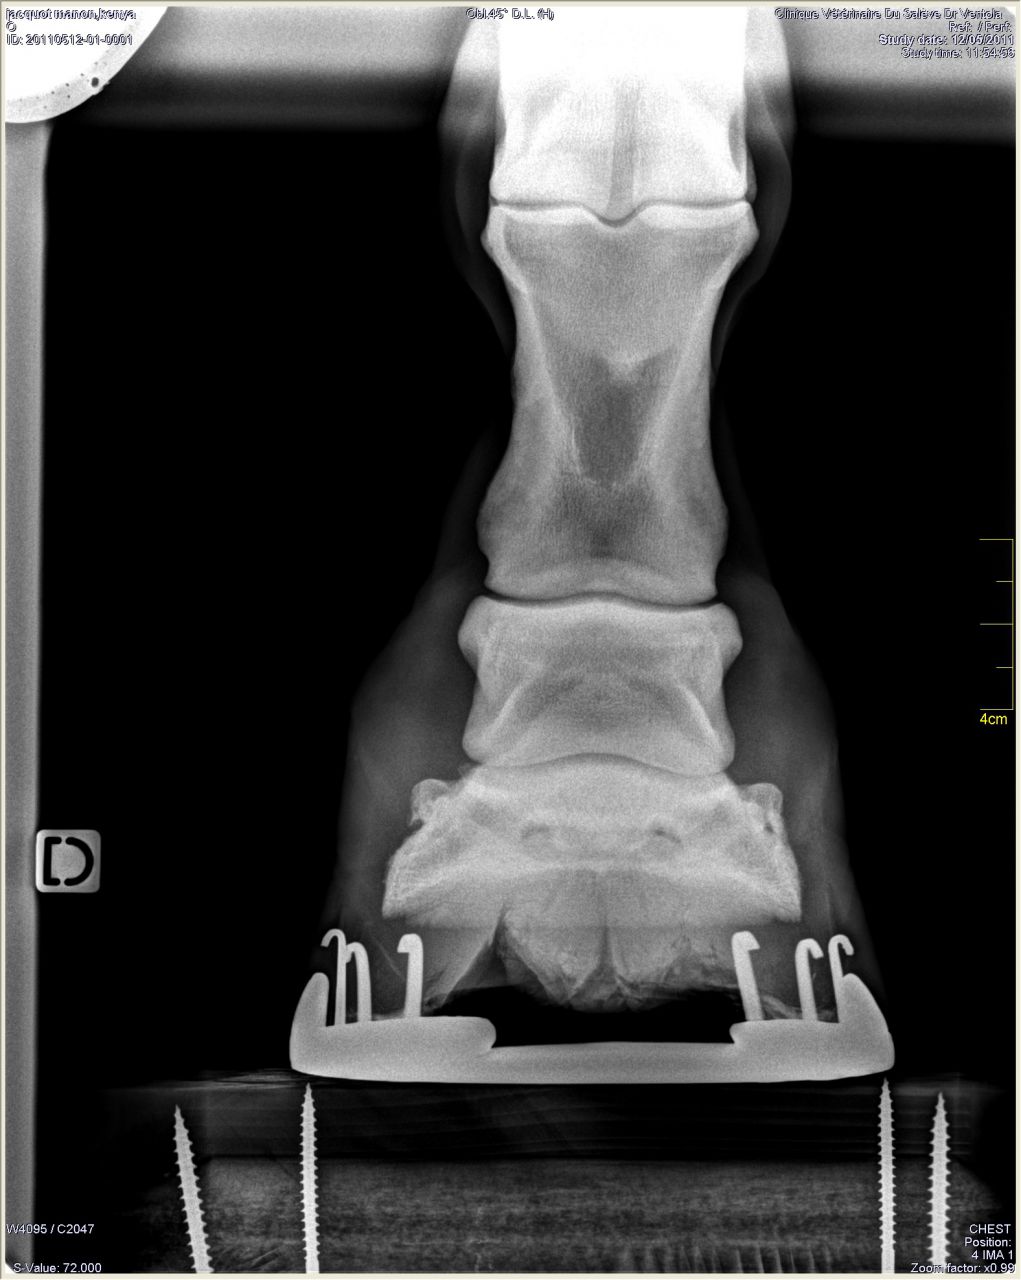

| Dire merci | Antérieur droit de profil: RAS à part le même problème de répartition du pied![]() De face à plat: ![]() De face en extension: ![]() |